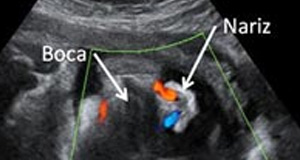

Semana 34 de embarazo: Qué ve la ecografía

Muchos centros realizan la ecografía del tercer trimestre con 34 semanas de embarazo, y esta es la última que se te realizará en el embarazo. De hecho, la Sociedad Española de Ginecología y Obstetricia (SEGO) recomienda hacer la ecografía del tercer trimestre entre las semanas 34 y 36. Es fundamental para valorar el correcto crecimiento fetal, la cantidad de líquido amniótico y el grado de envejecimiento de la placenta. Se observan en el bebé además, signos de madurez fetal, como las asas intestinales, y estructuras de la cabeza como las circunvoluciones del cerebro.

Importante: Recuerda no ponerte ese día cremas hidratantes o antiestrías ni aceites en la tripa, pues disminuyan la calidad de la imagen al transmitirse peor los ultrasonidos de la ecografía.